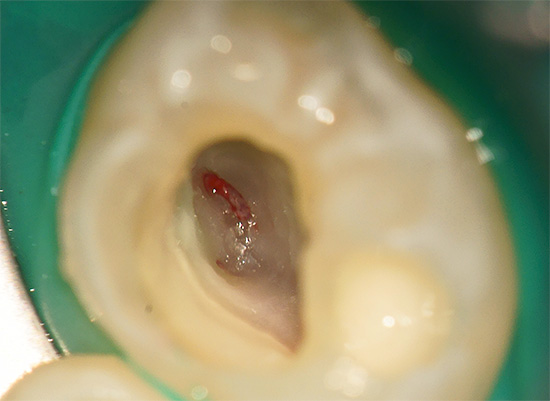

L'importanza principale nel trattamento completo della pulpite è il buon trattamento farmacologico dei canali e il loro riempimento fino all'apice fisiologico (apice). Per fare questo, è necessaria l'anestesia, i canali vengono elaborati con strumenti speciali simili agli aghi (lime), lavati con soluzioni antisettiche e sigillati con paste indurenti con o senza perni di guttaperca.

Dopo aver determinato la pulpite, il medico elabora un piano per il suo trattamento. Esistono 3 approcci al trattamento della pulpite: con la conservazione dell'intero "nervo", con la sua parziale rimozione, con l'estrazione completa della polpa dal sistema dei canali equini.

Il primo modo per mantenere l'intera polpa in uno stato vitale non è attualmente popolare a causa di frequenti complicazioni, quindi i medici di solito preferiscono quest'ultima opzione. Viene anche utilizzata la rimozione parziale della polpa, ma solo quando non c'è modo di attraversare l'intero canale a causa della sua struttura complessa o della presenza di corpi estranei in esso.